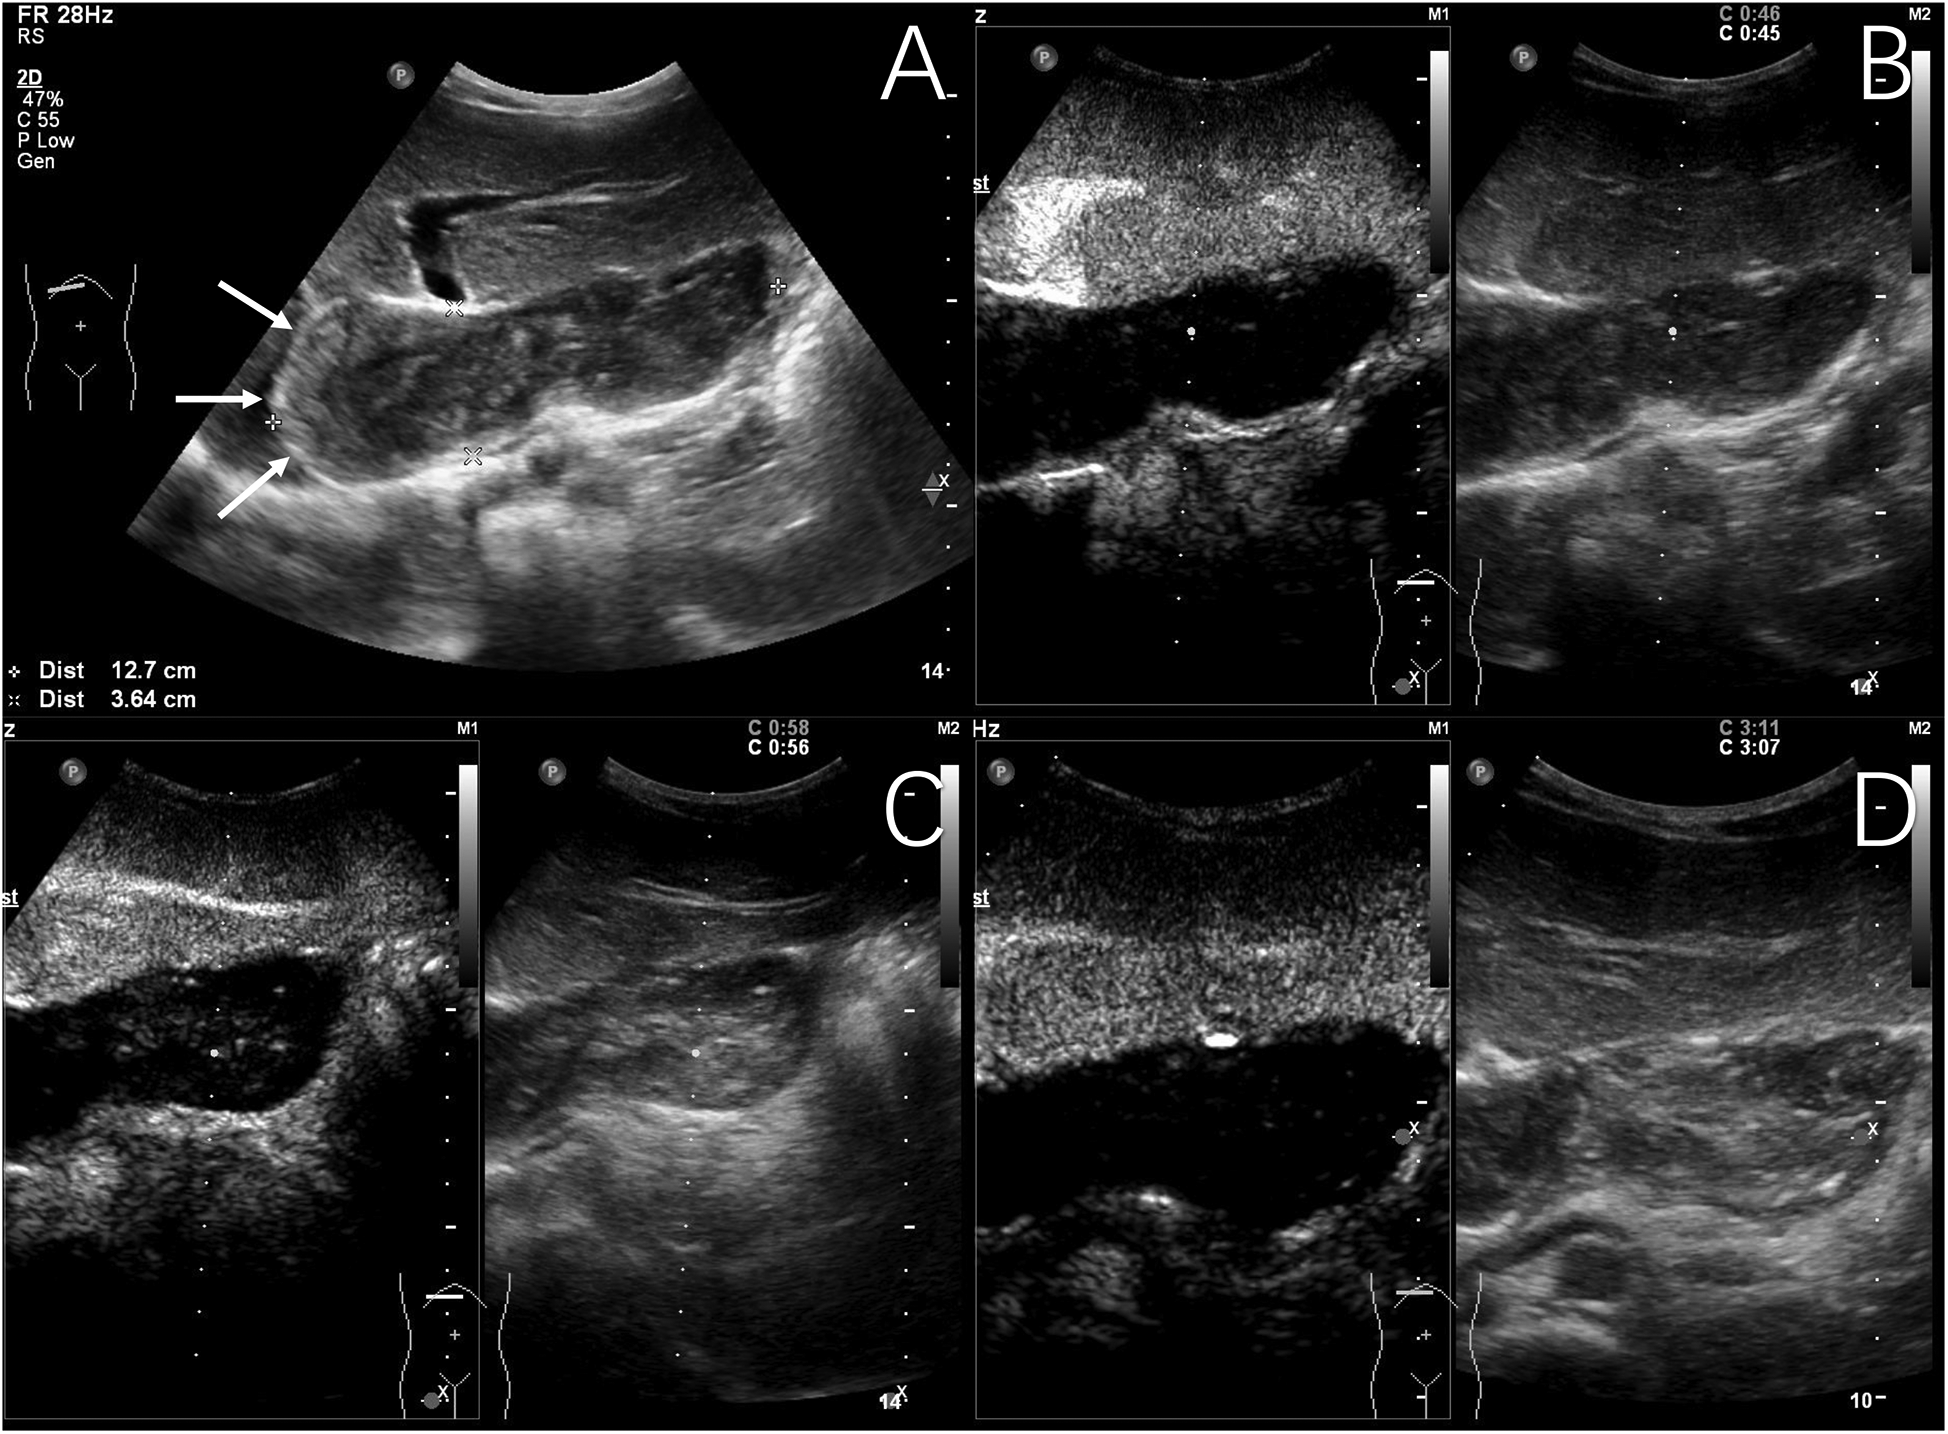

Two out of 31 children of hepatic echinococcosis underwent CEUS. Nine out of 36 children with hepatoblastoma underwent CEUS. One hepatic CE lesion showed no significant enhancement during the arterial, portal venous, and late phases (Figure 2). One hepatic AE lesion showed slight peripheral enhancement during the arterial phase (Figure 3). Nine hepatoblastoma lesions showed hyperenhancement during the arterial phase, six lesions began to washout in the portal venous phase, and nine lesions showed hypoenhancement in the late phase (Figure 4).

Figure 3

www.frontiersin.org

Figure 3. Typical ultrasound findings of hepatic alveolar echinococcosis (case 2). Ultrasound showed a 101 mm hyperechoic mass in the right liver, with unclear boundaries, irregular shape, and patchy strong echoes inside (A) contrast-enhanced ultrasound examination showed slight peripheral enhancement during the arterial phase (B), with no enhancement observed internally in the arterial phase, portal venous phase (C), or late phase (D) (The white arrows indicate the peripheral slightly hyperenhanced sign of the lesion in the arterial phase).